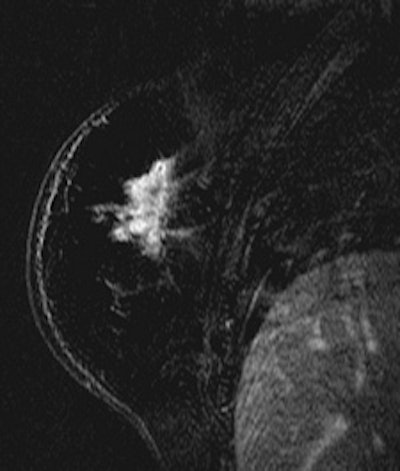

| Patient with breast cancer (invasive ductal carcinoma, grade II). MR-subtracted images (three minutes after contrast medium injection) before (left) and at the end (right) of the neoadjuvant chemotherapy. Initial staging: unifocal infiltrating cancer. After treatment, even if there is a decrease in size of the cancer, its long axis (RECIST) is unchanged with a multifocal shrinkage of the tumor. Unsuccessful first breast-conserving surgery, then mastectomy. Image courtesy of Dr. Anne Tardivon. |